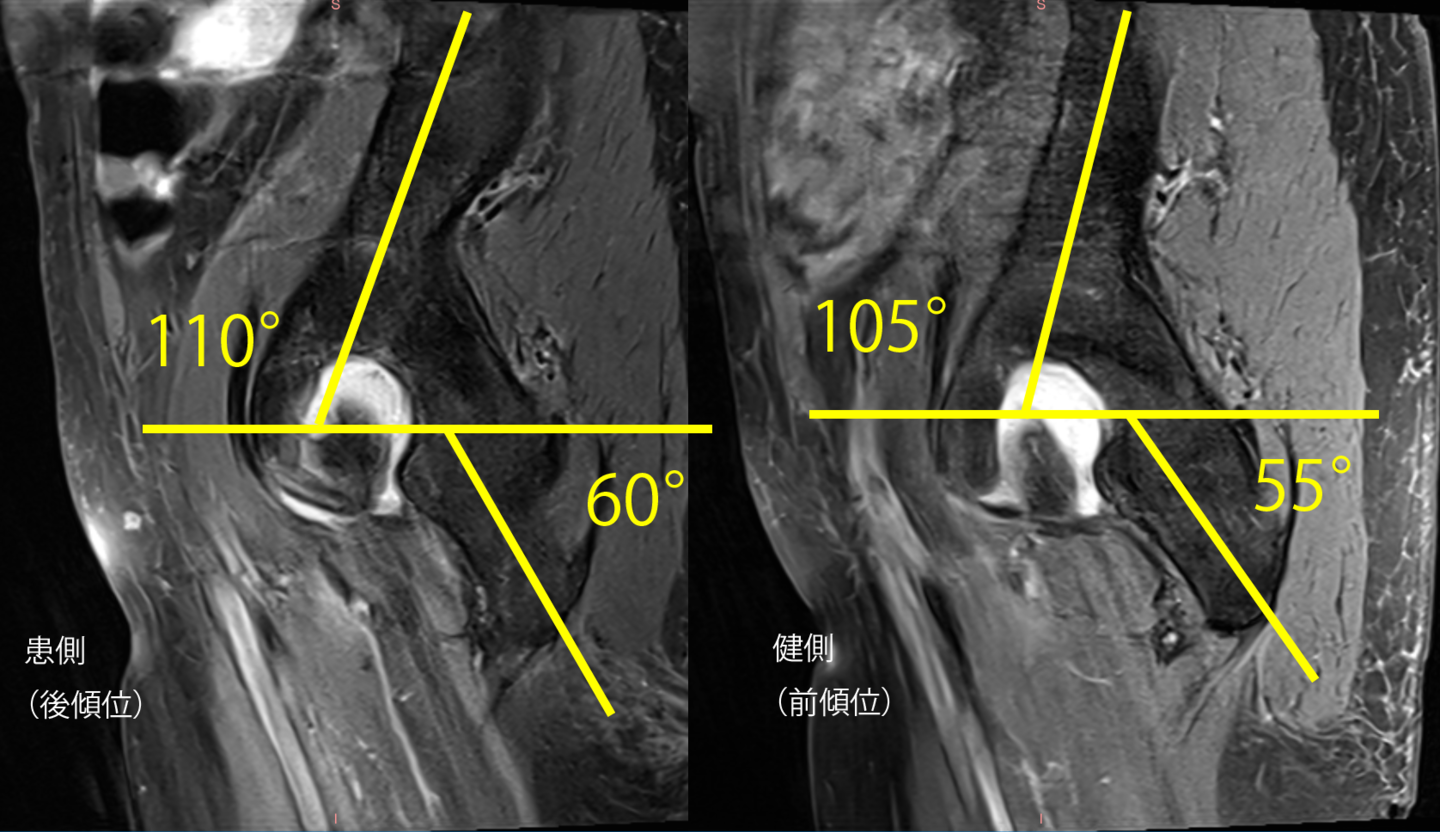

③3Dモデリングで痛みや動きを分析

病態を理解し、適切な治療を行うためには、関節の構造を理解し、体の深部に影響を与えることが出来なければなりません。そのためにも3Dモデリングを使うことが非常に役に立つことがわかりました。もし画像所見をお持ちでしたらお借りできますと幸いです。

スポーツ障害難治性のスポーツ障害では、動作解析と機能解析を組み合わせが重要です。 |